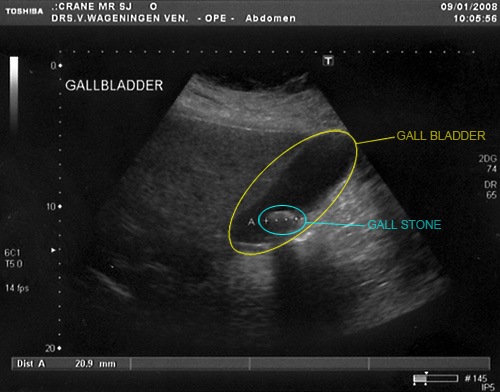

I have been getting episodes of acute abdominal pain accompanied by fever on and off for at least 6 months. This past week saw me wake up with one on Saturday and have another on Sunday evening. I went to see the doctor who decided that it sounded like problems with my gallbladder and arranged a sonar examination. This confirmed a 2cm gallstone and I saw a specialist today who will operate to remove my gall bladder next Thursday. In lieu of any new photographs here is what my sonar results look like.

gallstone